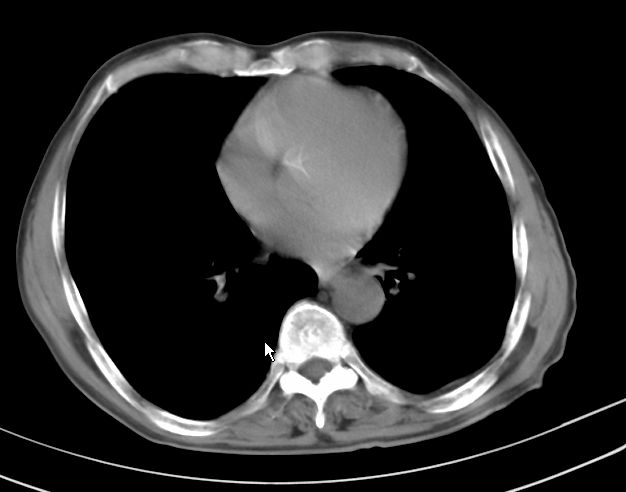

标题: CT17095:胸部病变请大家看看是什么性质的

请大家看看是什么性质的。炎性病变首先考虑哪一种炎症。

支持右肺上叶前段\\下叶内基底段感染,建议抗炎治疗后复查,除外结核.

支持右肺上叶前段\\下叶上段感染,建议抗炎治疗后复查,除外结核.

支持右肺上叶前段、下叶内基底段感染,建议抗炎治疗后复查,除外结核.

右肺上叶前段及下叶内基底段感染性病变;建议抗炎治疗后复查。

楼主说是炎症,凭啥?典型的周围型肺癌(腺癌可能性大),肝内可能已有转移,强化看看吧。